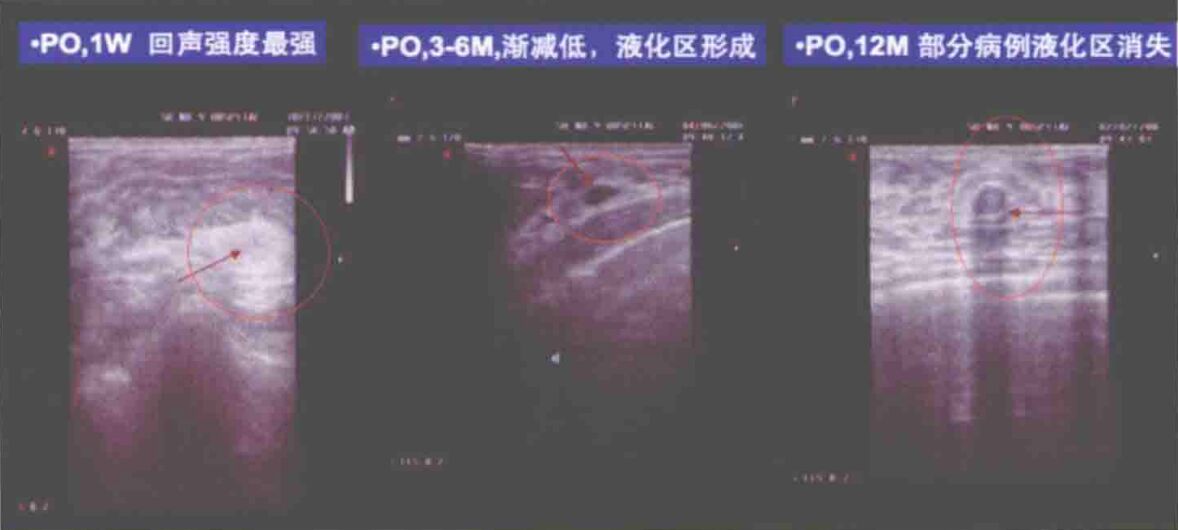

①超声表现:移植早期,如术后3个月时.移植脂肪在超声中呈现为中强回声团,部分团块中心区有无回声区。如图为超声特征:

术后1年以后,囊肿形成,如有薄壁囊肿,超声表现为中心液化区有包囊的、有側后声影的圆形占位。厚壁囊肿超声表现为内部不均匀回声,有附壁结节显示为中高回声。有时内部可见沉淀样中强回声区,随体位变化。

囊肿可位于腺体后层-、胸大月JL内、腺体同、皮下。如病损行彩色多普勒探测,可见内部无血流信号,有时在低回声后方有回声轻度增强。